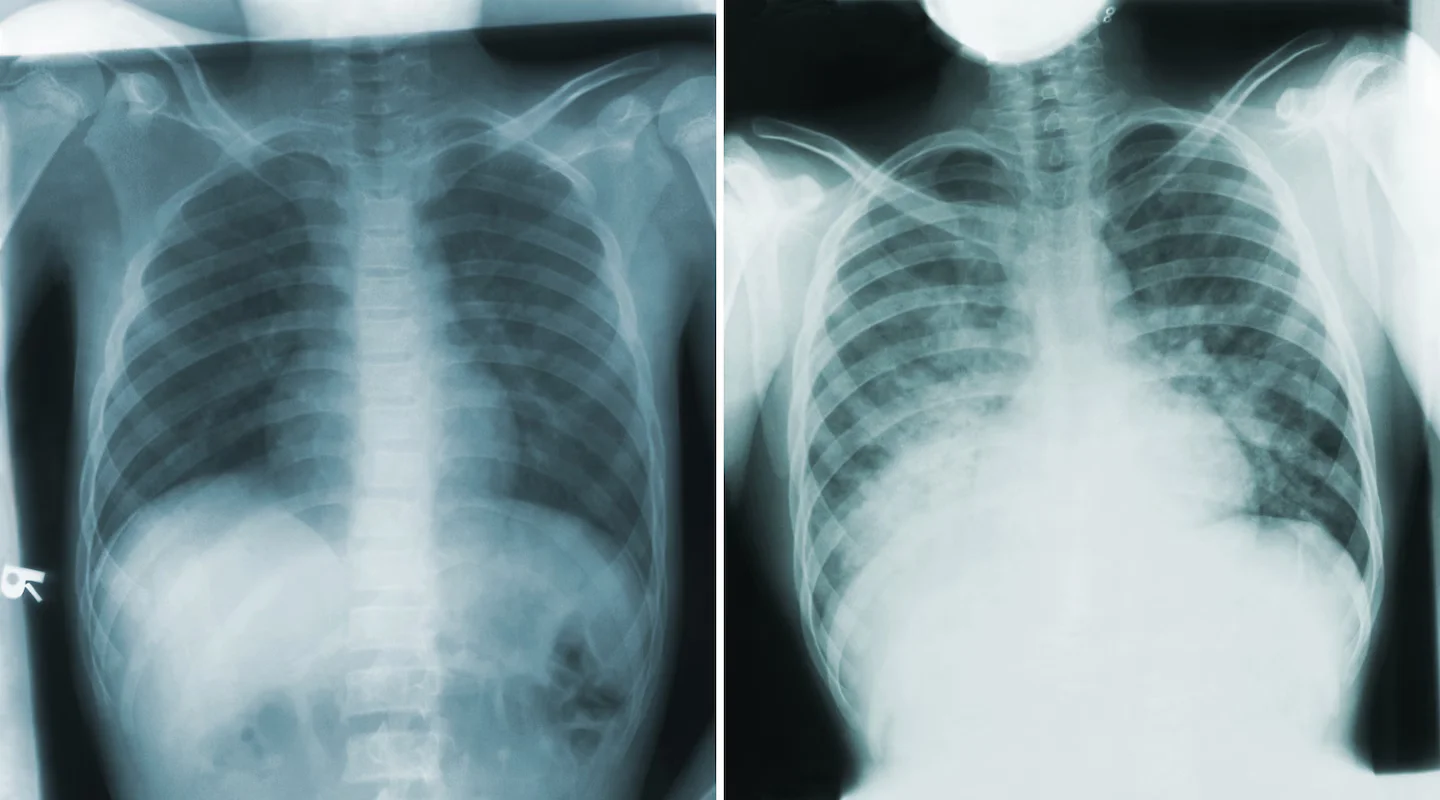

A recent death from plague in Arizona highlights that the disease, caused by Yersinia pestis and existing in three forms, still poses a health threat despite its rarity today. The pneumonic form, which is highly contagious, was responsible for the death, but there is no current evidence of further spread. Plague can be effectively treated with antibiotics if caught early, and the risk to Australia remains low due to the absence of the bacteria in local animals.